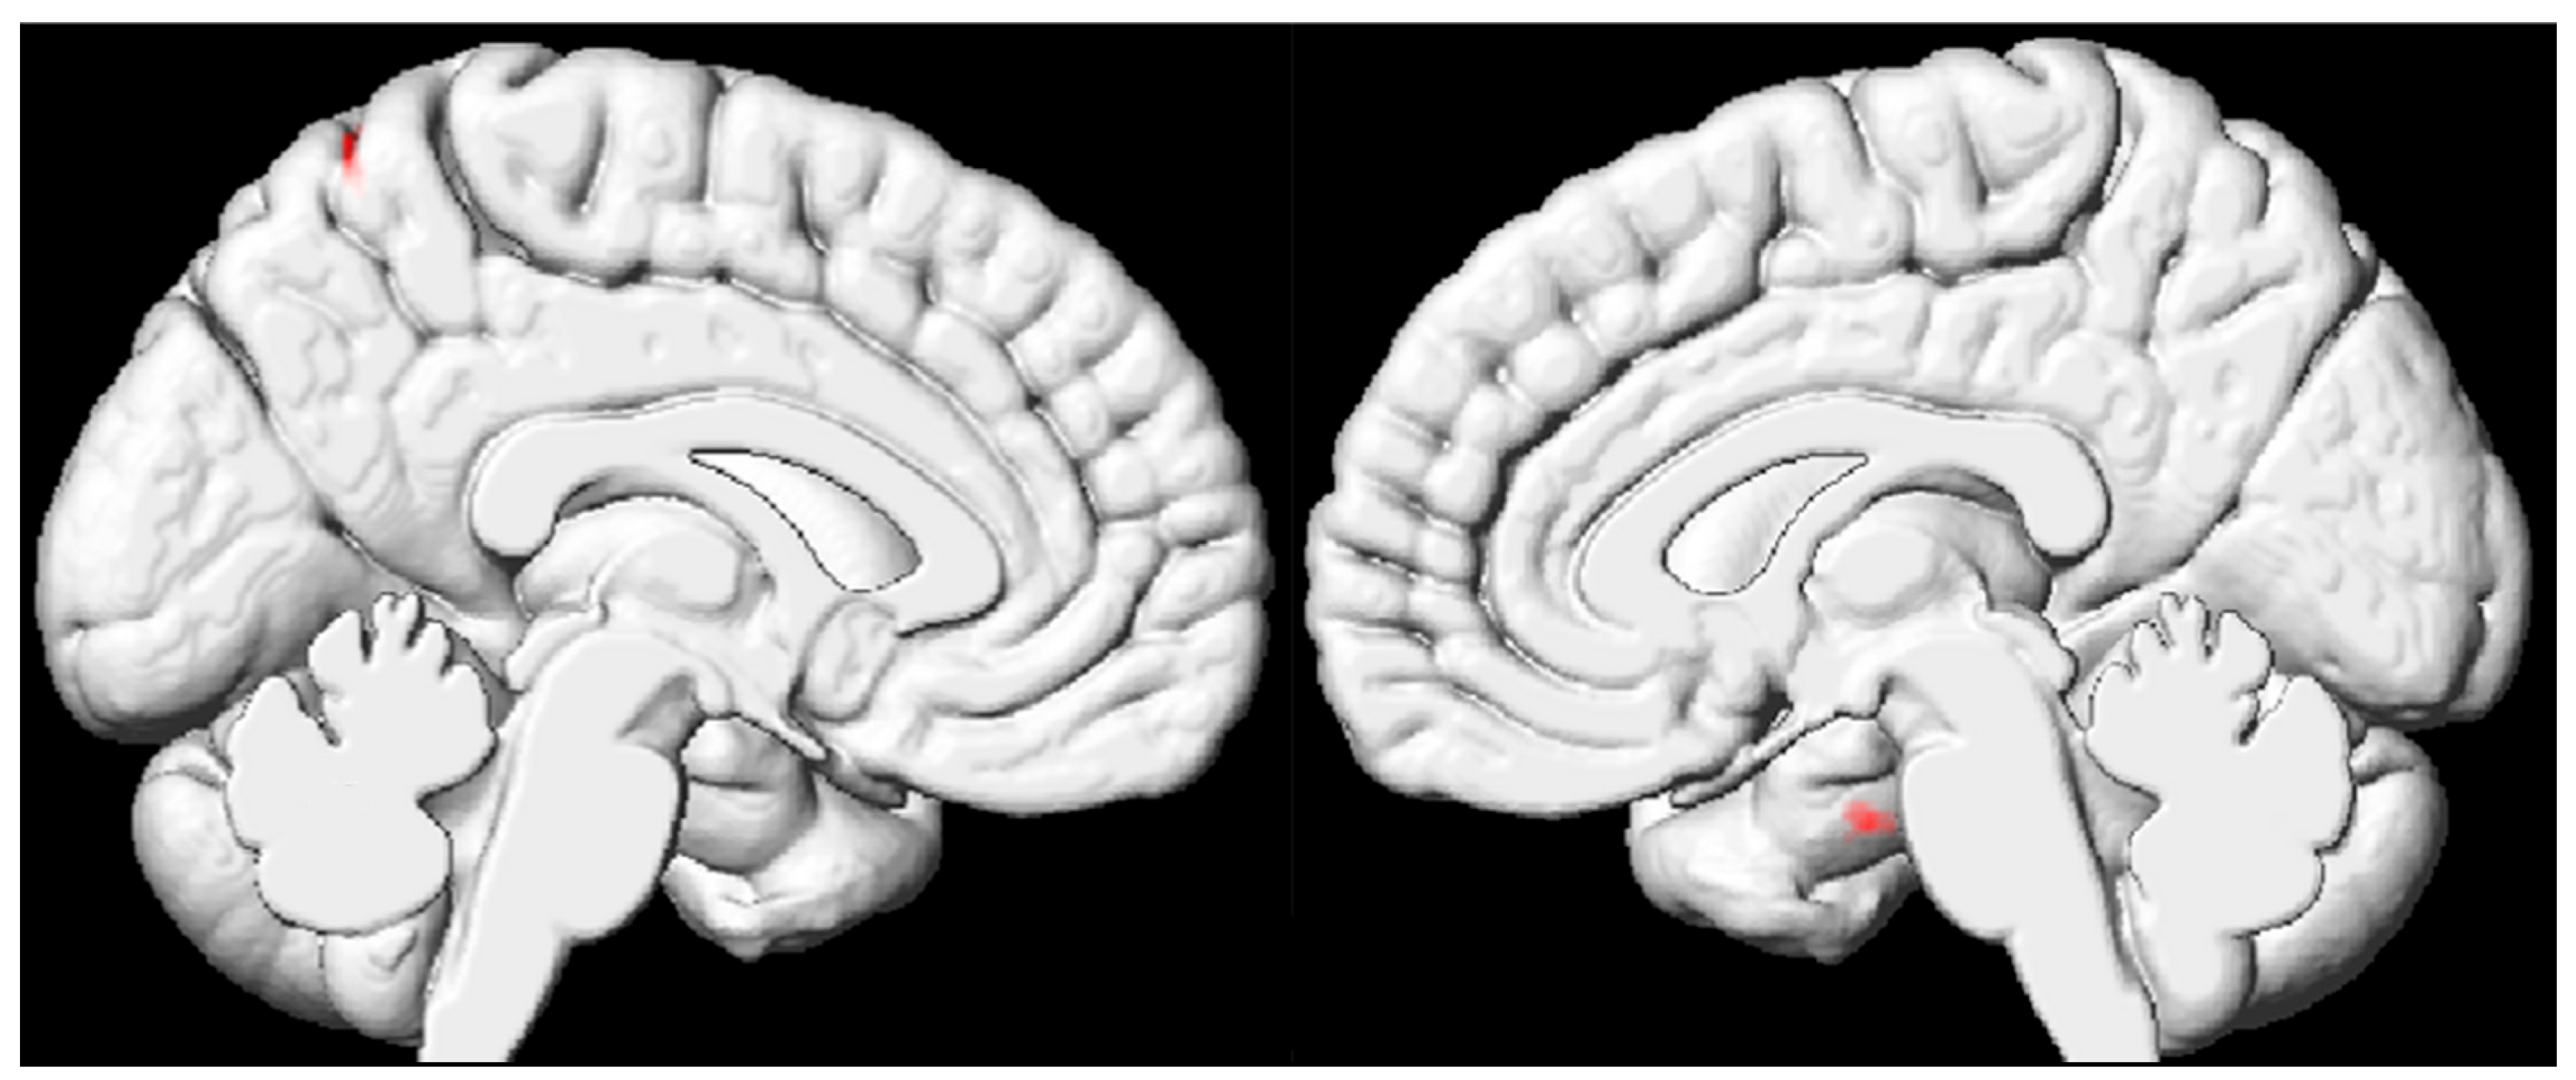

3.3. VBM Results Based on the Whole Brain of Pediatric FCD Patients

| Brain Region (AAL) | Cluster Size (Voxel) | Peak MNI Coordinates | t Value | ||

|---|---|---|---|---|---|

| x | y | z | |||

| FCD < HC | |||||

| Cluster 1 | |||||

| Right hippocampus | 26 | 19.5 | −9 | 33 | −4.4148 |

| Cluster 2 | |||||

| Left precentral gyrus | 20 | −13.5 | −61.5 | −64.5 | −5.1828 |